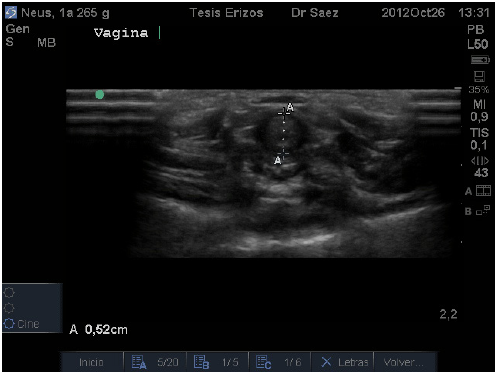

La vagina fue la primera porción en visualizarse y encontrándose en ella dos segmentos distintos, evaluados en corte transverso. El primero de ellos corresponde a una estructura tubular, hipoecoica, de granulado fino y homogéneo (FIG. 1). El segundo segmento, craneal al anterior, corresponde a una estructura con forma de óvalo plano, donde, en algunas ocasiones, fueron diferenciables tres capas: siendo la más interna hiperecoica que correspondería a presencia de mucus intraluminal, la banda media hipoecoica y la más externa hiperecoica (FIG. 2).

En algunos individuos se visualizó una región hipo o anecoica, la que correspondería a líquido presente en el interior del lumen, lo que en pequeñas cantidades podría considerarse como normal. Estos segmentos descritos corresponderían a vagina media y alta, respectivamente. La no visualización de la tercera porción de la vagina, correspondiente a la vagina baja, indicaría que este segmento se encontraría intrapélvico, lo que impediría su evaluación mediante ecografía. La diferencia de forma y diámetro entre los segmentos medio y alto de la vagina, esquematizados también por Reeve [11], podría deberse a que éste órgano, al estar formado por paredes musculares y no presentar contenido, como por ejemplo una gestación, que haga mantener su forma tubular, pasa a colapsarse y formar un óvalo plano.